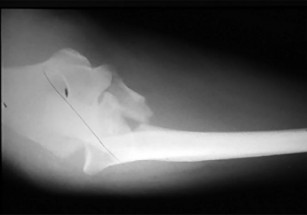

- الأشعة السينية (X-rays): هي الخطوة الأولى في تقييم الكسور، الخلوع، وتغيرات التهاب المفاصل. تساعد في تحديد مدى تدهور العظام والمسافات المفصلية. على سبيل المثال، تُظهر صور الأشعة السينية كسور السلاميات

. - الأشعة المقطعية (CT Scan): توفر صوراً تفصيلية ثلاثية الأبعاد للعظام، وهي مفيدة جداً لتقييم الكسور المعقدة، مثل كسور العظم الخطافي (Hamate Hook Fracture) التي قد لا تظهر في الأشعة السينية العادية

، أو لتقييم مدى تدهور العظم في حالات مثل مرض كينبوك. - التصوير بالرنين المغناطيسي (MRI): ممتاز لتقييم الأنسجة الرخوة مثل الأربطة، الأوتار، الأعصاب، والعضلات. يكشف عن التمزقات،